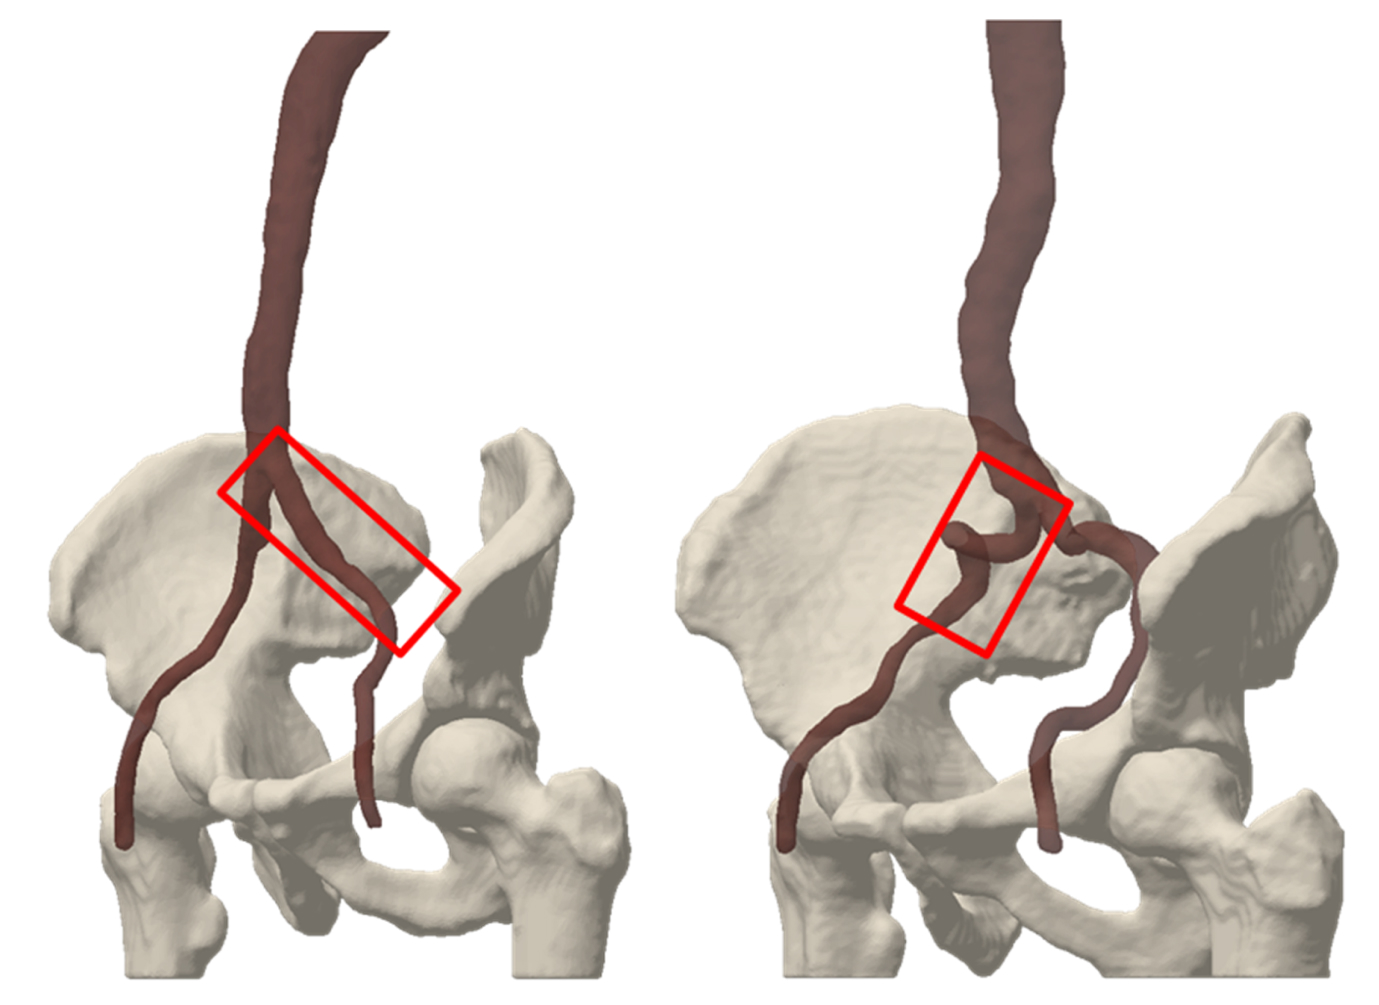

Create your own virtual patient population that fits to your implant using our extensive database. Detailed criteria allow for a proper selection of the target population.

Anatomy study02

Better understand your target anatomy with the help of virtual models, morphological and statistical analysis and simulations.

Virtual implantation 03

Visualize your device in highly-accurate anatomy models of humans and animals, prior to manufacture.

Advanced anatomical simulations04

Simulate your device in the entire virtual target population to investigate how these body variations may affect the performance and safety of your device.